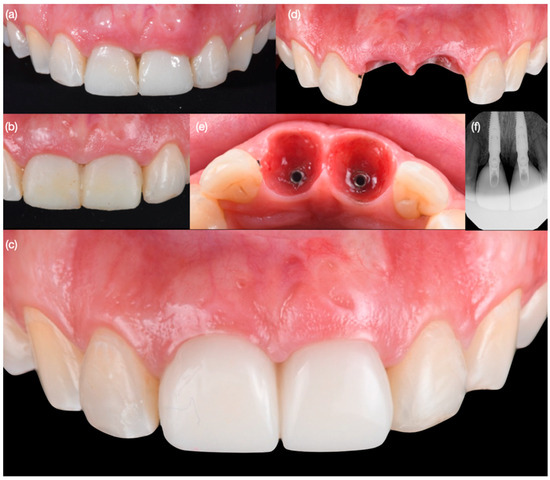

Figure 8. Soft tissue contouring at (a) 1 month after surgery, (b) recontoured provisional restoration at 2 months, (c) new provisional restoration at 3 months, (d) soft tissue after 3 months—frontal view and (e) incisal view, and (f) implant radiographs at 3 months.

Diagnostic three-dimensional digital scans (iTero Lumina, San Jose, CA, USA) of the maxilla and mandible were taken, and a traditional facebow record (Artex Facebow, Amann Girrbach, Koblach, Austria) was obtained. Printed models (Phrozen Sonic Mini 8K Resin 3D Printer, Phrozen Technology, Hsinchu City, Taiwan) were then fabricated and mounted on a semi-adjustable articulator (Artex CR, Amann Girrbach, Koblach, Austria). A diagnostic wax-up was performed and mounted in the articulator. The patient also received an intra-oral mock-up with a putty index guide (Elite P&P, Zhermack, Badia Polesine, Italy). An initial CBCT scan and the intra-oral scan were used to digitally plan the implant placement (Exocad DentalCAD, Darmstadt, Germany) and print the surgical guide (Phrozen Sonic Mini 8K Resin 3D Printer, Phrozen Technology, Hsinchu City, Taiwan) (Figure 3). Atraumatic tooth extractions were performed for both maxillary central incisors with the use of a periotome (Anterior Straight PT6, Hu-Friedy, Chicago, IL, USA) and forceps (Upper Anterior Atlas FAF1IS, Hu-Friedy, Chicago, IL, USA), only providing vertical forces, and avoiding any horizontal force (Figure 4). The extraction sockets were cleaned thoroughly with curettes (Universal Curette, Hu-Friedy, Chicago, IL, USA), and the abscess cavity was irrigated with saline solution and chlorohexidine to flush out all the debris and blood. The 3D-printed surgical guide was placed in position, osteotomies were performed, and two implants (3.5 mm diameter; 11.50 mm length, Helix GM, Neodent, Basel, Switzerland) were placed at the planned depth (Figure 5 and Figure 6). An autogenous soft tissue graft was harvested from the palate and positioned on the facial surface of the maxillary left side implant using polyethylene sutures. Interim abutments (Gm Temporary Abutments for Crown, Neodent, Basel, Switzerland) were placed with screw-retained non-occluding interim crowns (Figure 7). The patient had regular follow-up evaluations at 2, 4, 7, and 10 weeks, and at 3 and 4 months, after the implant placement. The provisional restoration was recontoured at week 10, and new sets of interim restorations were made at 3 and 4 months (Figure 8). The patient and clinicians were fully satisfied with the contour obtained with the last set of provisional restorations at 4 months, and it was decided to continue the final stage of the treatment (Figure 9).